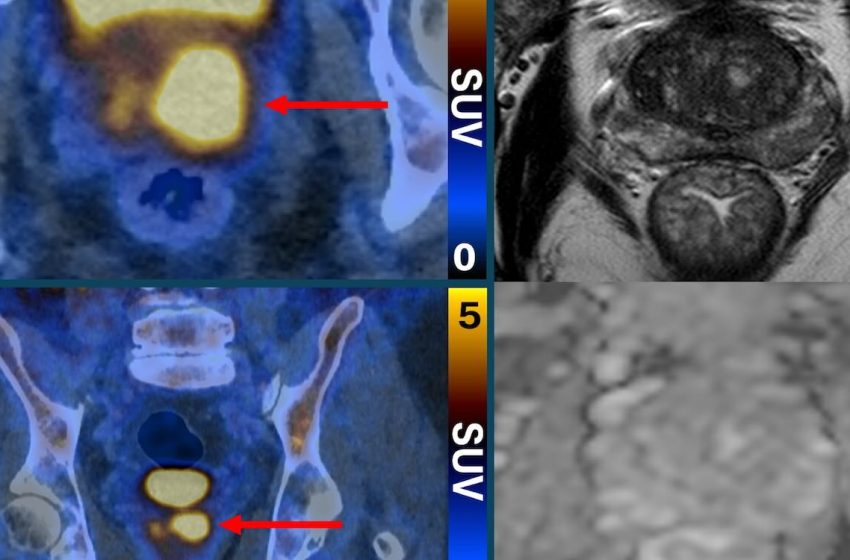

The state of the art imaging test uses a molecule that binds to prostate cancer cells, causing them to “light up in a remarkable way”—appearing as bright spots in the scanning image.

Their PSMA PET/CT scan identifies the more aggressive prostate cancer cells, which are potentially harmful and may need treatment—and could help reduce the risk of over-diagnosis by determining which cancers are low-risk and will never cause harm.

For patients who still needed a biopsy, their scan results ensured the procedure was targeted to the suspicious areas identified in the test to minimize complications and improve accuracy.

“PSMA PET/CT scanning makes prostate cancer cells light up in a remarkable way, particularly in more aggressive cancers,” said Dr. Buteau.

“Our findings show that PSMA PET/CT after MRI offers a ‘belt-and-braces’ approach that can determine which people have a clinically significant cancer, and which people are at low risk and don’t need a biopsy or further testing.”